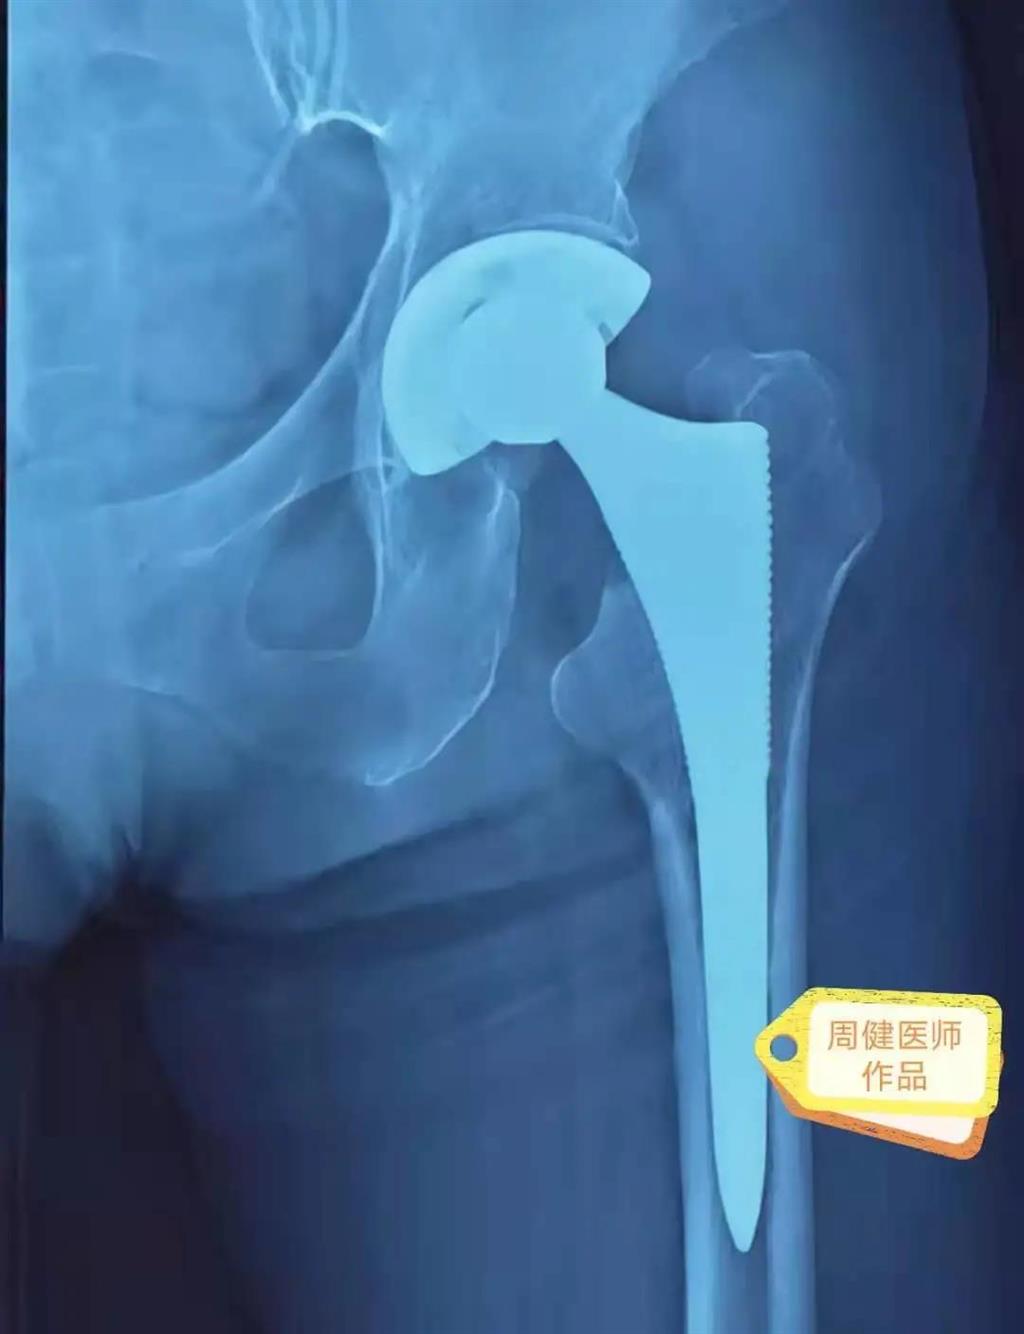

6月30日的“關節(jié)置換術”,患者是一位上了年紀的老人,苦于病痛折磨多年的他四處“求醫(yī)問藥”,最后在多位專家醫(yī)師及病友地力薦下選擇了和平國際醫(yī)院,在醫(yī)師團隊“偷天換日”般的手術后,老人成功告別了苦纏多年的病痛。

周健說,這場“關節(jié)置換術”對于他們團隊而言其實算是比較普通的手術,因為做過很多同類的手術,成功案例繁多,因此在手術操作上有較多地實操經驗。“不過話雖如此,作為醫(yī)生我們對于每一場手術都會全力以赴,這是為醫(yī)者的職責也是義務。”